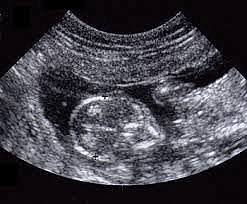

Le développement de la motrice et des sens du cerveau aux périodes prénatales dépend, comment la mère se nourrit et prend soin de leur corps pendant ce temps. Si elle fume, consomme les drogues ou l’alcool ça va affecter le bébé énormément quand ils sont nés, physique ou mentale. Des problèmes de santé mentale, leur système nerveux, être prématuré ou le risque d'avoir des malformations congénitales, etc. C'est important pour la mère de prendre certaines vitamines pour que le bébé reste en santé

Les cinq sens ne développent pas tout en même temps, c'est graduel. En premier, le toucher développent dans le liquide amniotique de la mère. Ensuite, l'odorat et le goût se développent. Par la suite, l'ouïe se développe pendant le 26e et la 28e semaine d'aménorrhée (26 ou 27e semaine de la grossesse) et la vue le suit. Pendant le début, 5 à 6 mois de la grossesse, le fœtus entend déjà des sons. Le cortex visuel et auditif est presque mature à la naissance